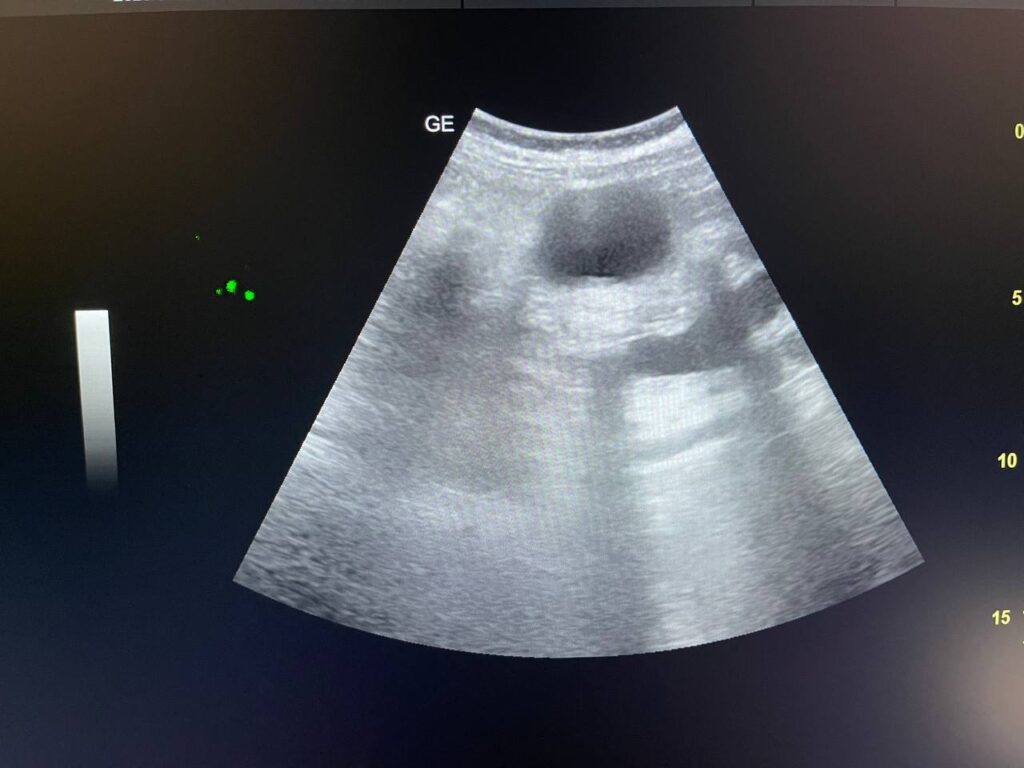

GB STONES & CBD STONE

Gall bladder distended,  increase wall thickness 5.5mm edematous, contain multiple mobile stones of variable sizes , the largest 12mm + dilated common bile duct 13mm , due to presence of stone about 25mm in the distal part